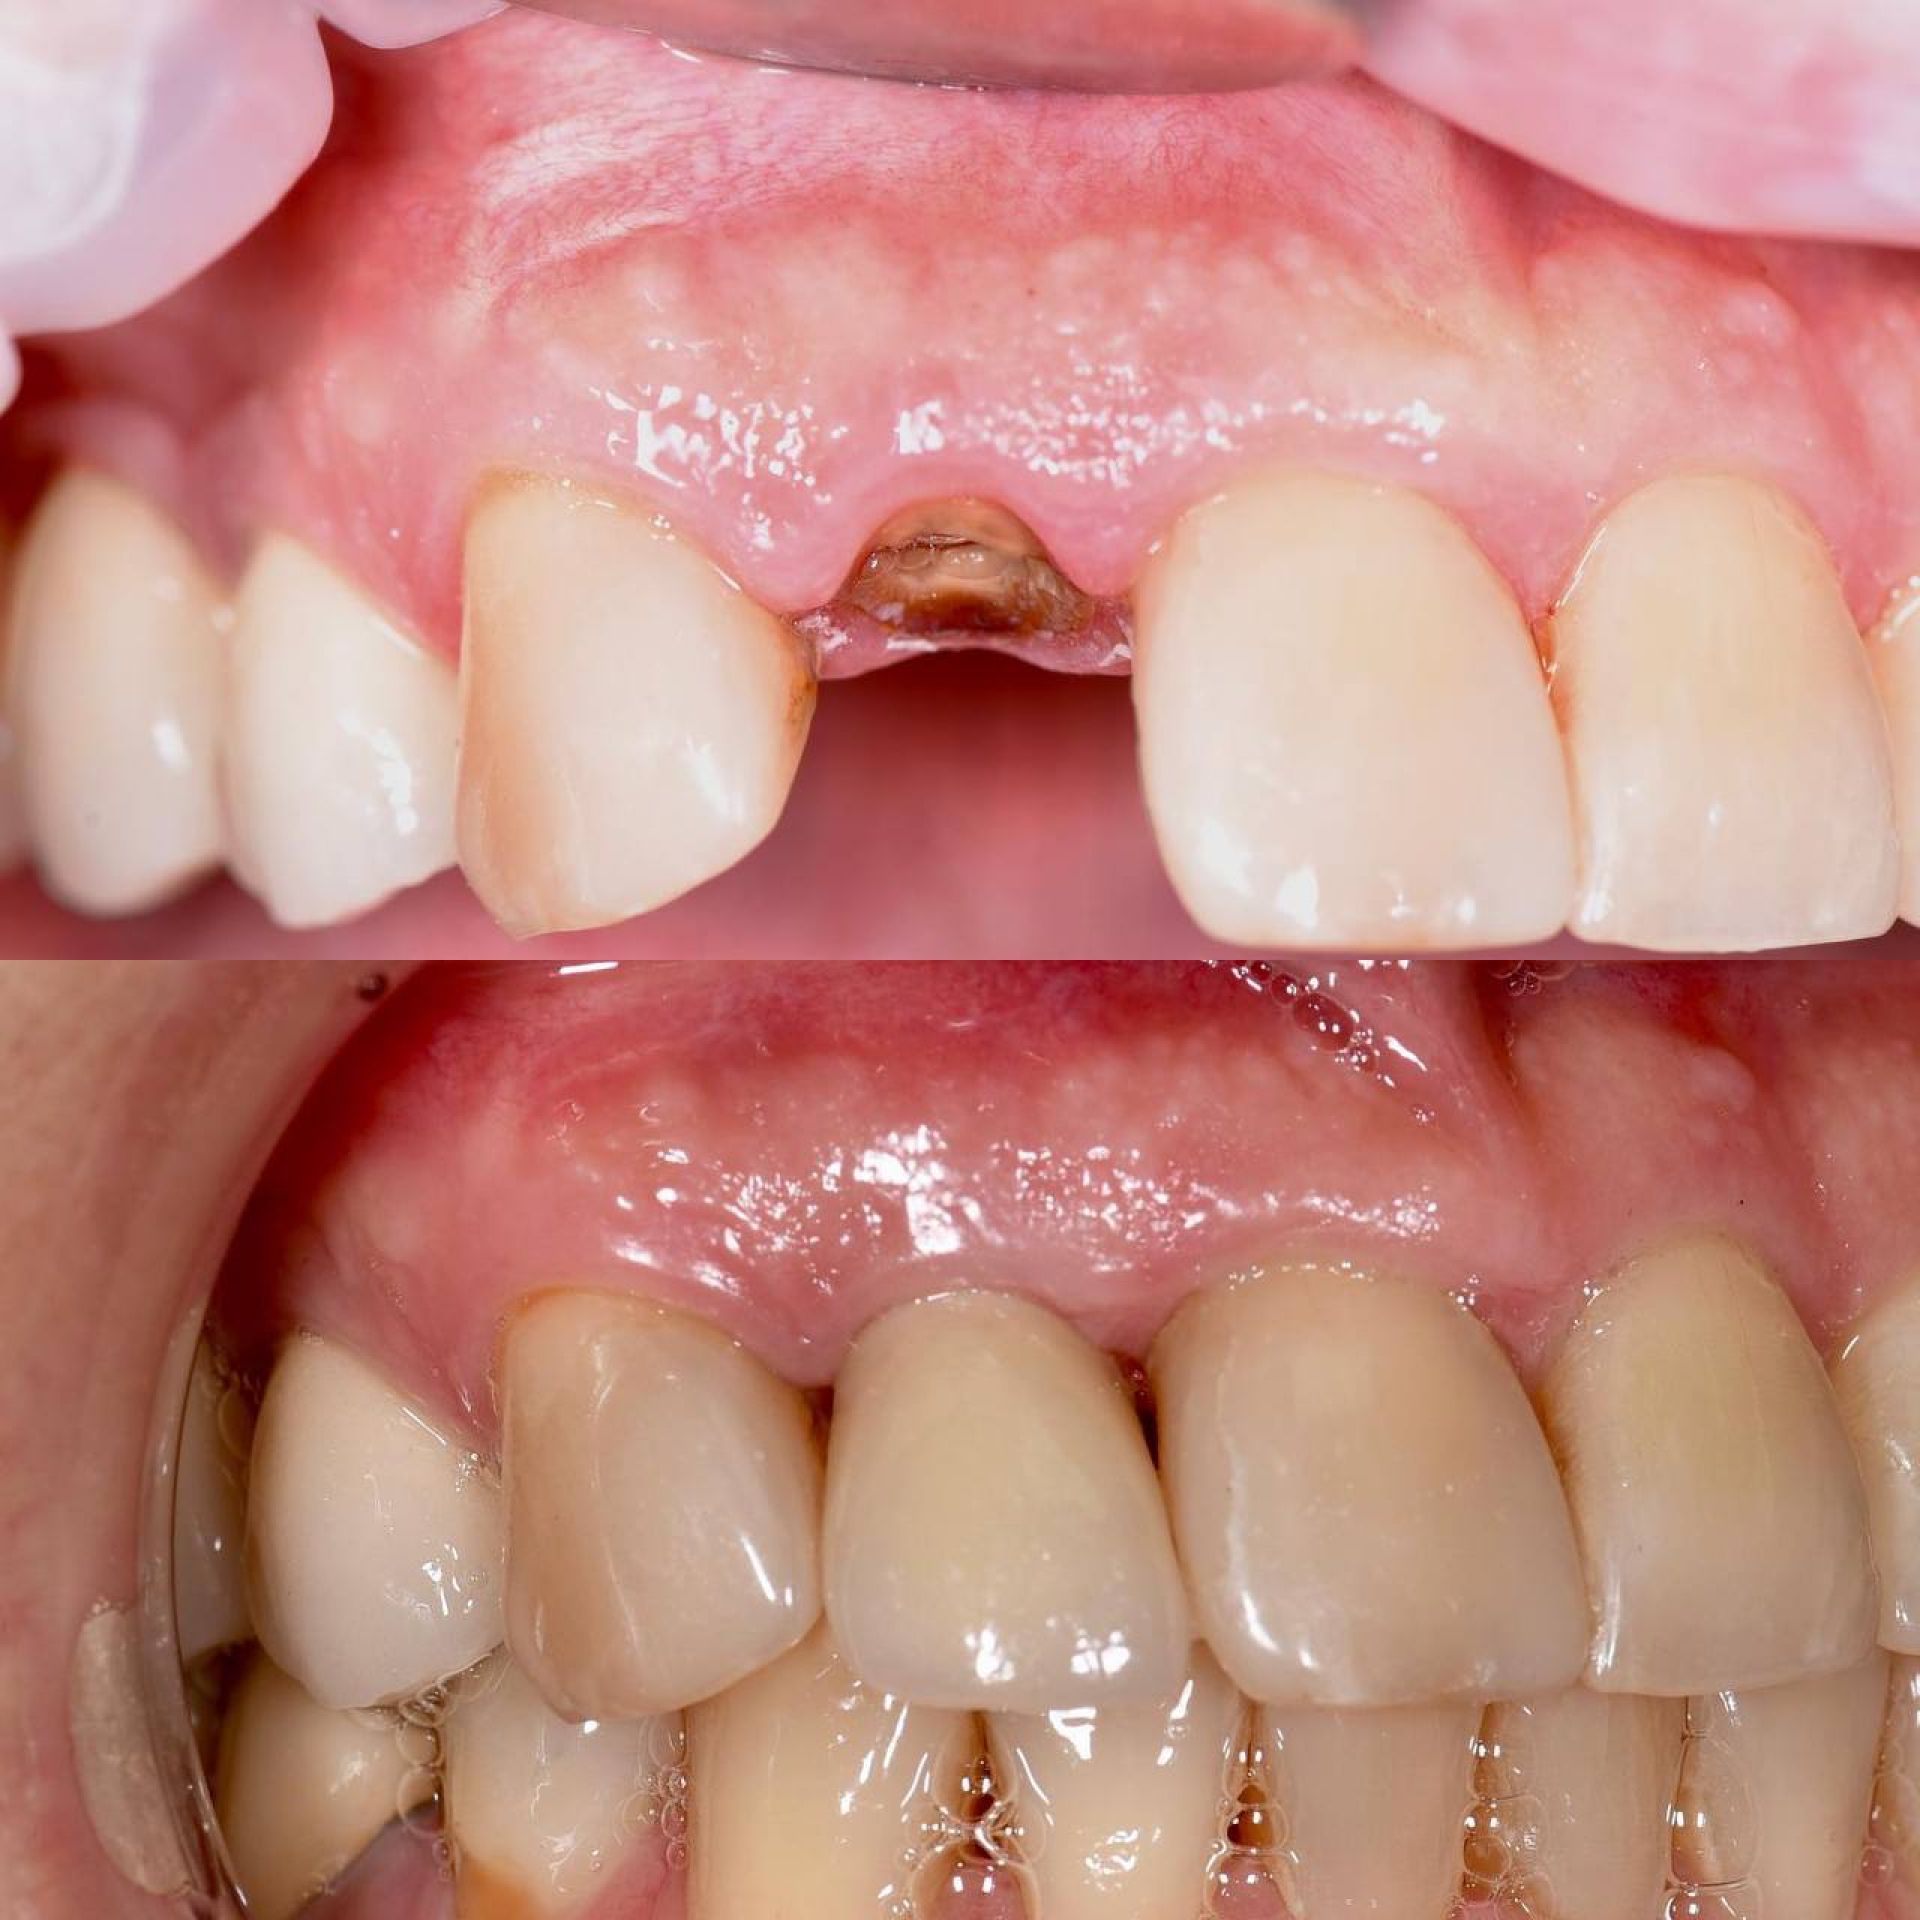

Імплантація полягає у встановленні штучного зубного кореня та відновленні коронки за допомогою ортопедичної конструкції. Операція виконується під анестезією, що робить її абсолютно безболісною. Процес відновлення після операції відбувається швидко, що дозволяє вам швидко повернутися до звичайного життя.

Однією із переваг, які пропонує «Стоматологія Олексюка», є негайна імплантація. Цей метод дозволяє встановити імплантат безпосередньо після видалення пошкодженого зуба. Такий підхід гарантує високу точність і швидке відновлення, оскільки кістка ще не зазнала деформацій.

Імплантація зубів — це сучасна технологія відновлення зубного ряду, яка використовується для заміщення втрачених зубів. Цей процес полягає в установці штучного корінця зуба, відомого як імплантат, у кістку щелепи, на який потім кріпиться внутрішньоротова частина — коронка.

Завдяки імплантатам Ви назавжди забудете про дискомфорт, який спричиняє відсутній зуб або зуби. Ми якісно відновимо жування та естетику Вашої посмішки в найкоротші терміни з довготривалим результатом.